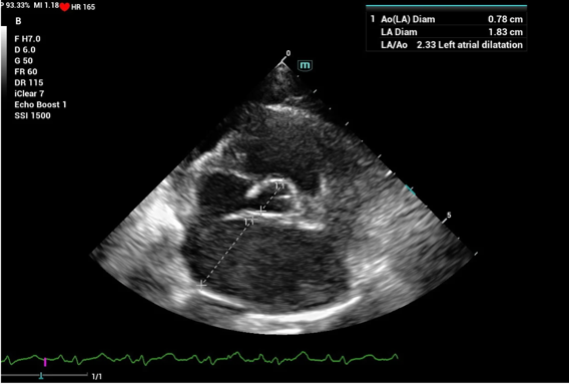

Kích thước và chức năng nhĩ trái

Việc đo đạc kích thước nhĩ trái (LA) rất quan trọng với bệnh lý cơ tim bên trái, bao gồm HCM. Tình trạng giãn nhĩ trái nặng đồng nghĩa mèo đã bị suy tim trái hoặc mèo có rủi ro cao bị suy tim trái. Điều này có thể dẫn tới tình trạng ứ máu và hình thành cục máu đông (Thrombus), thường xảy ra ở tiểu nhĩ trái (LAA) và có thể gây ra thuyên tắc động mạch (ATE).

Đo kích thước nhĩ trái thường được sử dụng qua phép đo LA:Ao. Kích thước bình thường của chỉ số này thường <1.6, khi giá trị này >1.8-2.0 hoặc đường kính LA > 18-19mm thì mèo sẽ có nguy cơ phát triển suy tim và/hoặc thuyên tắc động mạch (ATE – giai đoạn B2).

LA là một cấu trúc 3 chiều, một số con mèo thường giãn nhiều ở tiểu nhĩ nhưng giãn ít ở nhĩ trái hoặc nhĩ trái thường lớn hơn ở mặt cắt tại mỏm tim bên trái so với mặt cắt cạnh ức phải. Do đó, nhĩ trái nên được khảo sát cả từ mặt cắt ức phải và mỏm tim trái. Các chỉ số khác cũng có thể được đánh giá ở mèo bị suy tim trái như tốc độ dòng máu qua tiểu nhĩ trái và tốc độ sóng A qua van hai lá thường giảm.